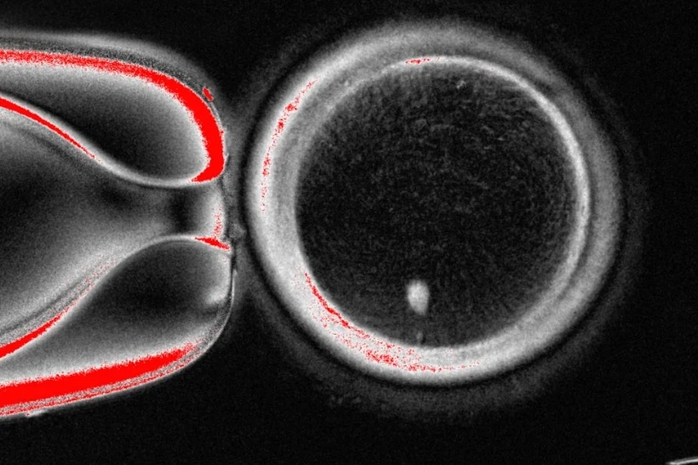

Hình ảnh dưới kính hiển vi của một trứng người có chứa nhân được lấy từ tế bào da. Ảnh do Phòng Thí nghiệm Mitalipov tại ĐH Y tế và Khoa học Oregon (Mỹ) cung cấp Ảnh: AP

Thế nhưng, tế bào da có đến hai bộ nhiễm sắc thể trong khi trứng và tinh trùng lẽ ra mỗi loại chỉ có một bộ để kết hợp lại trong quá trình thụ tinh. Vì vậy, các nhà nghiên cứu đã kích thích những tế bào giống trứng này loại bỏ bớt nhiễm sắc thể thừa, sau đó tiêm tinh trùng từ người hiến tặng vào và thúc đẩy tiến trình phát triển sau thụ tinh.